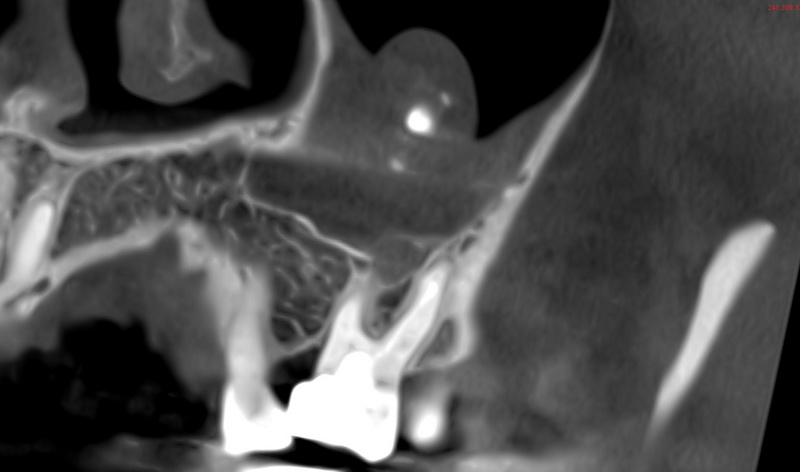

Було прийняте рішення про видалення зуба тільки після обстеження КЛКТ. При огляді знімка була виявлена проблема на верхній щелепі.

Проблема заключається у новоутворенні у гайморовій пазусі яке називається міцетома.

У проекції новоутворення є у минулому лікований зуб з наявним хронічним запаленням на верхівці коренів. Однією із причин даного новоутворення може бути саме неякісне лікування з використанням неякісних пломбувальних матеріалів для кореневих каналів.